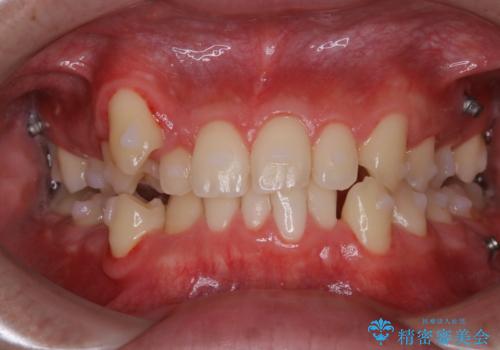

ワイヤー矯正中に歯の染め出し